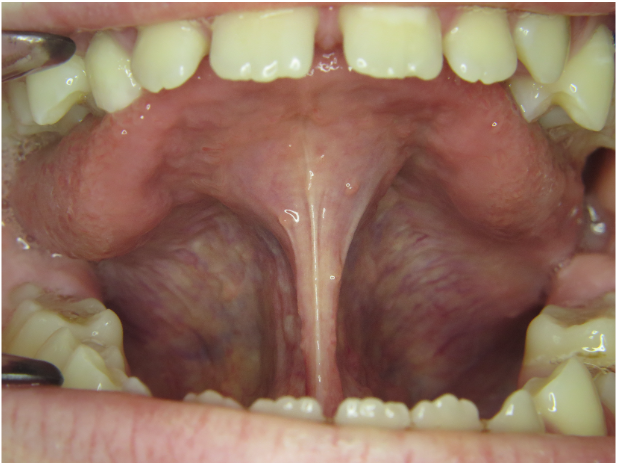

Wir sagten es bereits an anderer Stelle – Bilder sagen mehr als 1000 Worte…

Die Galerie zeigt verschiedene Problemstellungen unserer Patienten von Anfang bis Ende:

mykie® macht’s möglich – sehen Sie selbst: